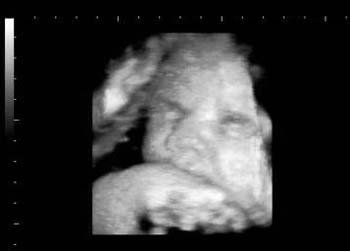

Baby Ultrasound Pictures

Baby ultrasound pictures are very special. 3D ultrasound in early pregnancy is useful for many reasons. It can show if the baby is developing normally, can determine size and approximate delivery date. They can do one as early as five weeks.The first one is usually ordered at about the 12th week and the sex can be determined at about the 18th week. The placenta can also be seen ( the organ that feeds the fetus ) as can the

amniotic fluid

( a protectant fluid against the fetus being bumped and temperature extremes ). We can see if the baby has down syndrome or if the mother has or will have complications later in the maternity. Later on, as the baby grows, it starts to do things like yawning and smiling. Here are some

Baby ultrasound pictures. Back to 3D ultrasound